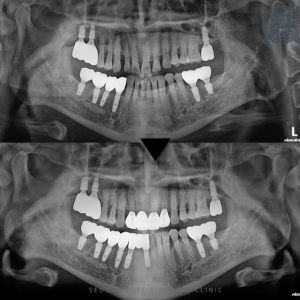

술전 사진

23.01.27

상악 전치부에서 보실 수 있듯이, 기존 브릿지 아래쪽의 뼈가 모두 소실되어 환자분이 웃을 때 치아 뿌리가 드러나는 상태였습니다. 단순히 치아 뿌리가 노출된 상태라면 일부 치료를 통해 회복이 가능할 수 있지만, 이미 하방에 심각한 우식이 발생해 색이 어두워지고, 기존 수복물은 더 이상 유지할 수 없는 상황이었습니다.

더욱이 주변 뼈까지 소실되면서 치아의 동요가 발생했고, 기존 브릿지를 재설치할 수 있는 상태가 아니었습니다. 따라서, 주변 뼈를 다시 채우는 골이식 수술을 진행하며, 전치부 브릿지 임플란트 치료를 계획하게 되었습니다.

술후 사진

24.02.28

이전에는 환자분이 기존 브릿지 때문에 크게 웃을 수 없을 정도로 많은 걱정을 하셨습니다. 하지만 이제 환자분은 자연스러운 임플란트 브릿지에 완벽하게 적응하셔서 자신 있게 웃을 수 있게 되었습니다.

브릿지 임플란트는 그 어떤 부위보다도 뛰어난 심미성이 요구됩니다. 그러나 심미성뿐만 아니라, 오랜 시간 동안 안정적인 임플란트를 유지하려면 철저한 골이식이 필수적입니다. 파노라마 사진을 통해 보실 수 있듯, 기존 브릿지 아래쪽의 골 상태와는 달리 훨씬 건강하고 좋은 골 상태를 확인할 수 있습니다.